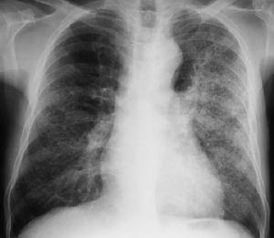

(一)胸部X線檢查:最常見表現(xiàn)為支氣管肺炎型改變,通常無助于肺炎病原的確定,但某些特征對診斷可有所提示,如肺葉實變、空洞形成或較大量胸腔積液多見于細(xì)菌性肺炎。

葡萄球菌肺炎可引起明顯的肺組織壞死、肺氣囊、肺膿腫和膿胸。革蘭陰性桿菌肺炎常呈下葉支氣管肺炎型,易形成多發(fā)性小膿腔。

對肺炎診斷有重要價值,炎性浸潤陰影的部位、范圍,有無空洞、胸腔積液等與病原菌有關(guān)。, 不同病原菌的肺炎X線表現(xiàn), , , X線表現(xiàn), 病原菌, , , 葉或段低密度片狀浸潤, 肺炎鏈球菌,流感嗜血桿菌,克雷白肺炎桿菌,大腸桿菌,軍團(tuán)菌, , , 均勻性浸潤(斑片或條索狀陰影), 肺炎支原體、病毒、厭氧和非厭氧菌混合感染、軍團(tuán)菌屬, , , 彌漫性均勻性浸潤或結(jié)節(jié)狀陰影, 軍團(tuán)菌屬、病毒、卡氏肺囊蟲病,分支桿菌屬,曲霉菌,念珠菌屬,血行播散性感染, , , 空洞性浸潤, 金黃色葡萄球菌,革蘭陰性菌,厭氧菌,結(jié)核桿菌,曲霉菌, , , (二)細(xì)菌學(xué)檢查:痰或胸水涂片檢查,培養(yǎng)致病菌及抗生素敏感試驗.連續(xù)2、3次為同一細(xì)菌生長,致病菌的可能性大,僅一次陽性或多次為不同細(xì)菌生長,則可靠性差。

常見白細(xì)胞增多,但血清LDH常正常。胸片示肺以葉或節(jié)段性分布或網(wǎng)狀結(jié)締狀浸潤,金葡菌感染可形成空洞。

此外,心力衰竭、有害氣體的吸入、長期臥床的肺水腫、肺淤血、以及腦外傷等都有利于細(xì)菌的感染和生長繁殖,導(dǎo)致肺炎。 肺炎的診斷: 血液檢查時末梢白細(xì)胞計數(shù)可達(dá)每立方毫米20000—30000,中性粒細(xì)胞增至80%以上,在實變期可見大片均勻致密的陰影,典型的分布限于肺段或肺葉,但大多數(shù)為片狀。

x線檢查對本病診斷很有幫助,但需盡早進(jìn)行。 肺炎的治療: 肺炎屬于急性感染性疾病,應(yīng)積極進(jìn)行抗炎治療。